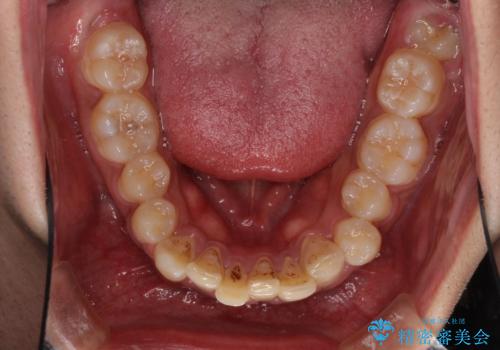

- 深い咬み合わせと前歯のデコボコを改善したいとのことで来院された患者様です。

咬合力が非常に強く、抜歯したスペースがなかなか閉じないであろうことは予想できましたが、思っていた以上に期間がかかりました。

前歯のすり減りも著しかったため、仕上げの位置の調整にも期間を要しました。